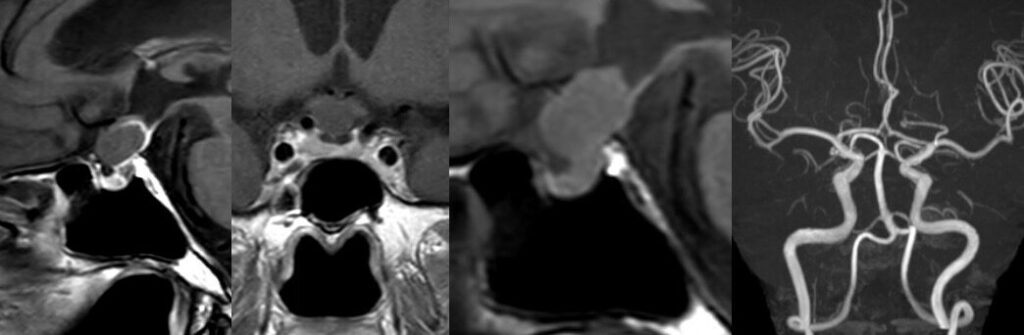

2026年1月 71歳女性の頭蓋咽頭種を内視鏡で摘出しました。 2026 3/01 聴神経・腫瘍 2026年3月1日川尻先生の執刀で嚢胞性かつ小型の頭蓋咽頭腫を内視鏡で摘出しました。新しく入局する高嶋浩央先生も手術に参加しました。術後髄液漏が生じ修復術が必要となりましたが、後遺症なく退院しました。学生らも熱心に見学していました。 聴神経・腫瘍 よかったらシェアしてね! URLをコピーしました! URLをコピーしました! 56歳女性 内頸動脈眼動脈分岐部動脈瘤クリッピング術をしました。軽度視野欠損が出ましたが無事退院されました。 260125日 大雪となりました。 この記事を書いた人 kikuta 関連記事 2604月、59歳女性の左海綿静脈洞内髄膜腫(複視)に対して左内頸動脈のための左STA-MCAバイパスを行いました。 2026年4月11日 260331 60歳男性 頭蓋咽頭腫を開頭で摘出しました。 2026年4月3日 260324 78歳男性 大型下垂体腺腫を外視鏡+内視鏡の複合手術を行いました。 2026年3月26日 2026年2月 74歳女性右聴神経腫瘍の手術を行いました。 2026年3月21日 37歳女性 下垂体線腫を内視鏡手術しました。両耳側の視野欠損が回復しました。 2025年12月27日 66歳大型の聴神経腫瘍、術中出血のため手術が難渋し時間がかかりました。過去最大級の難敵でした。 MRIだけでは分からないものです。 2025年12月16日 13歳小児の小脳腫瘍の摘出を行いました。術後失調や眼振が出ていましたが徐々に回復され大きな後遺症なく回復されました。よかったです。 2025年12月16日 27歳女性 第四脳室髄膜腫を手術しました。術後左顔面まひ、外転神経麻痺が出現しましたが、顔面は数日で治癒しました。 2025年12月6日